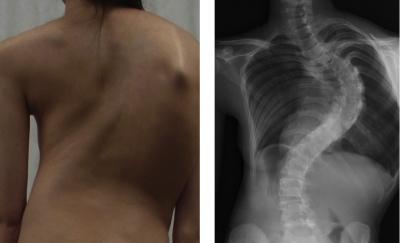

Researchers from the RIKEN Center for Integrative Medical Sciences in Japan have identified the first gene to be associated with adolescent idiopathic scoliosis (also called AIS) across Asian and Caucasian populations. The gene is involved in the growth and development of the spine during childhood.

AIS is the most common pediatric skeletal disease, affecting approximately 2% of school-age children. The causes of scoliosis remain largely unknown and brace treatment and surgery are the only treatment options. However, many clinical and genetic studies suggest a contribution of genetic factors.

The researchers show that the susceptibility gene, GPR126, is highly expressed in cartilage and that suppression of this gene leads to delayed growth and bone tissue formation in the developing spine. GPR126 is also known to play a role in human height and trunk length.

Picture caption: Girl with adolescent idiopathic scoliosis (left) and posterior-anterior standing x-ray of spine (right).